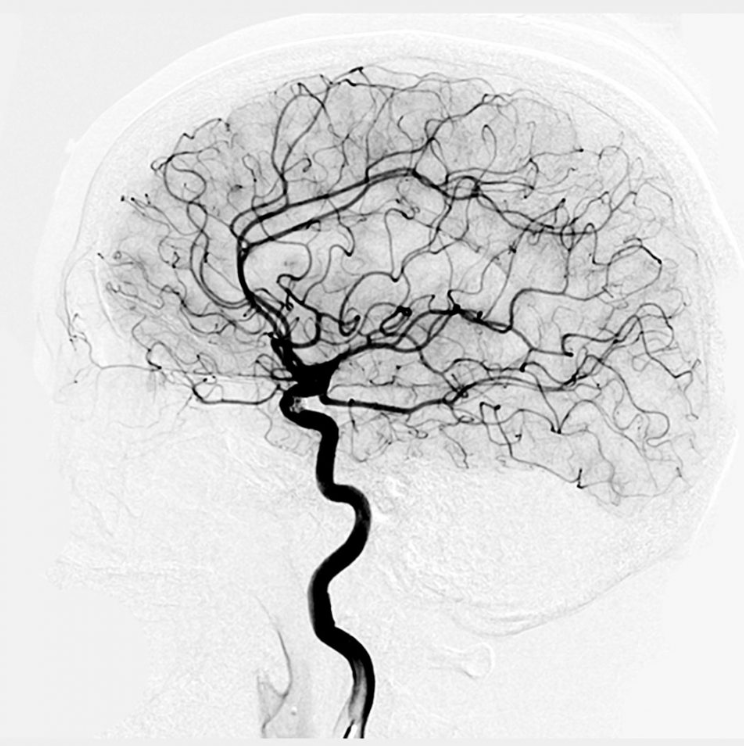

혈관 조영술은 혈관을 검사하기 위해 사용되는 엑스레이의 일종입니다.

일반적인 엑스레이로 사람을 촬영하게 되면 뼈만 보이게 되는데, 이는 뼈의 밀도가 다른 장기들에 비해 높기 때문입니다.

엑스레이는 밀도가 높을수록 잘 투과하지 못하는 성질을 가지고 있기에 비교적 밀도가 낮은 장기와 뇌, 혈관 등은 투과하고 뼈는 밀도가 높아 통과하지 못해 선명하게 볼 수 있는 것입니다.

그렇다면 밀도가 높은 무언가가 돌아다니면 혈관을 엑스레이로도 정밀하게 촬영할 수 있지 않을까 하는 의문에서 시작된 것이 바로 혈관조영술입니다.

- 카테터를 촬영을 원하는 부위까지 유도한 후, 카테터를 통해 특수한 염료(조영제)를 주입합니다.

- 염료가 혈관을 통과하면서 엑스레이가 촬영됩니다.